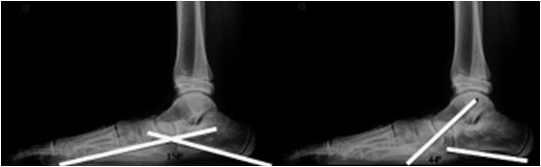

Para la evaluación de los pacientes con la posición valgo en el retropié (pes plano valgus) y marcado valgo flexible del retropié (pes calcáneo valgo), se realizó valoración radiológica pre y postoperatoria en las proyecciones dorso-plantar y lateral con carga, con el objetivo de medir los ángulos Costa Bartani, inclinación astragalina, y angulación del calcáneo4.

Se realizaron las mediciones radiológicas previamente descritas pre y postoperatorias en las cual se obtuvieron los resultados mostrados en la Tabla 1. En cuanto a la medición del ángulo Costa Bartani, los valores fueron Preoperatorio: 149°±5° y Postoperatorio: 126°±5°, p=0,02, el ángulo de inclinación del astrágalo Preoperatorio: 41°±7° y Postoperatorio: 24°±56°, p=0,04 y la angulación de calcáneo Preoperatoria: 12°± 5° y Postoperatoria: 15°±4 °, p=0,55.

| Ángulo Costa-Bartani (120°-125°) | 149°±5° | 126°±5º | 0,02 |

| Ángulo de inclinación astragalina (15°-20°) | 41°±7° | 24°±5º | 0,04 |

| Ángulo de inclinación del calcáneo (20°-30°) | 12°±5° | 15°±4° | 0,55 |

Entre los pacientes con pie plano flexible tratados con tornillo subtalar en nuestro estudio, el análisis de rayos X durante el período de seguimiento muestra buenos resultados en aproximadamente el 94% de los pacientes. Las mediciones de rayos X muestran una mejoría en los ángulos de inclinación Costa-Bartani y talar que del ángulo de inclinación del calcáneo en las proyecciones tomadas con carga, probablemente debido al sitio de corrección, es decir, la articulación subastragalina. Se observó una diminución en la pronación y se pudo mantener las angulaciones en rangos aceptables en cuanto al arco plantar y la bóveda cuando se tomaron proyecciones con carga, resolviendo la sintomatología en los pacientes atendidos